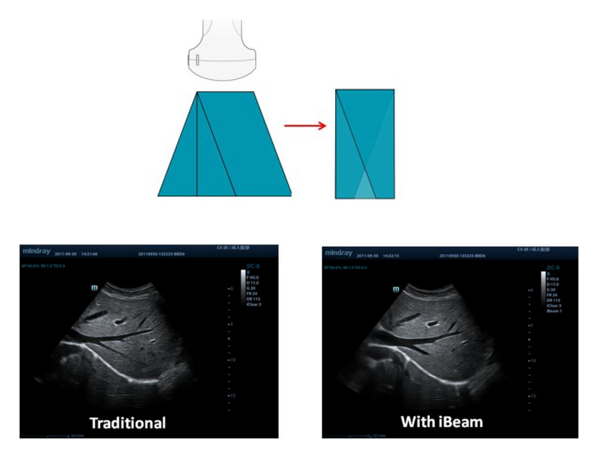

iBeam™

Permite utilizar varios ángulos de adquisición de imagen para formar una sola imagen, obteniendo así una resolución con contraste aumentada y una mejor visualización.

20161102111748_9729